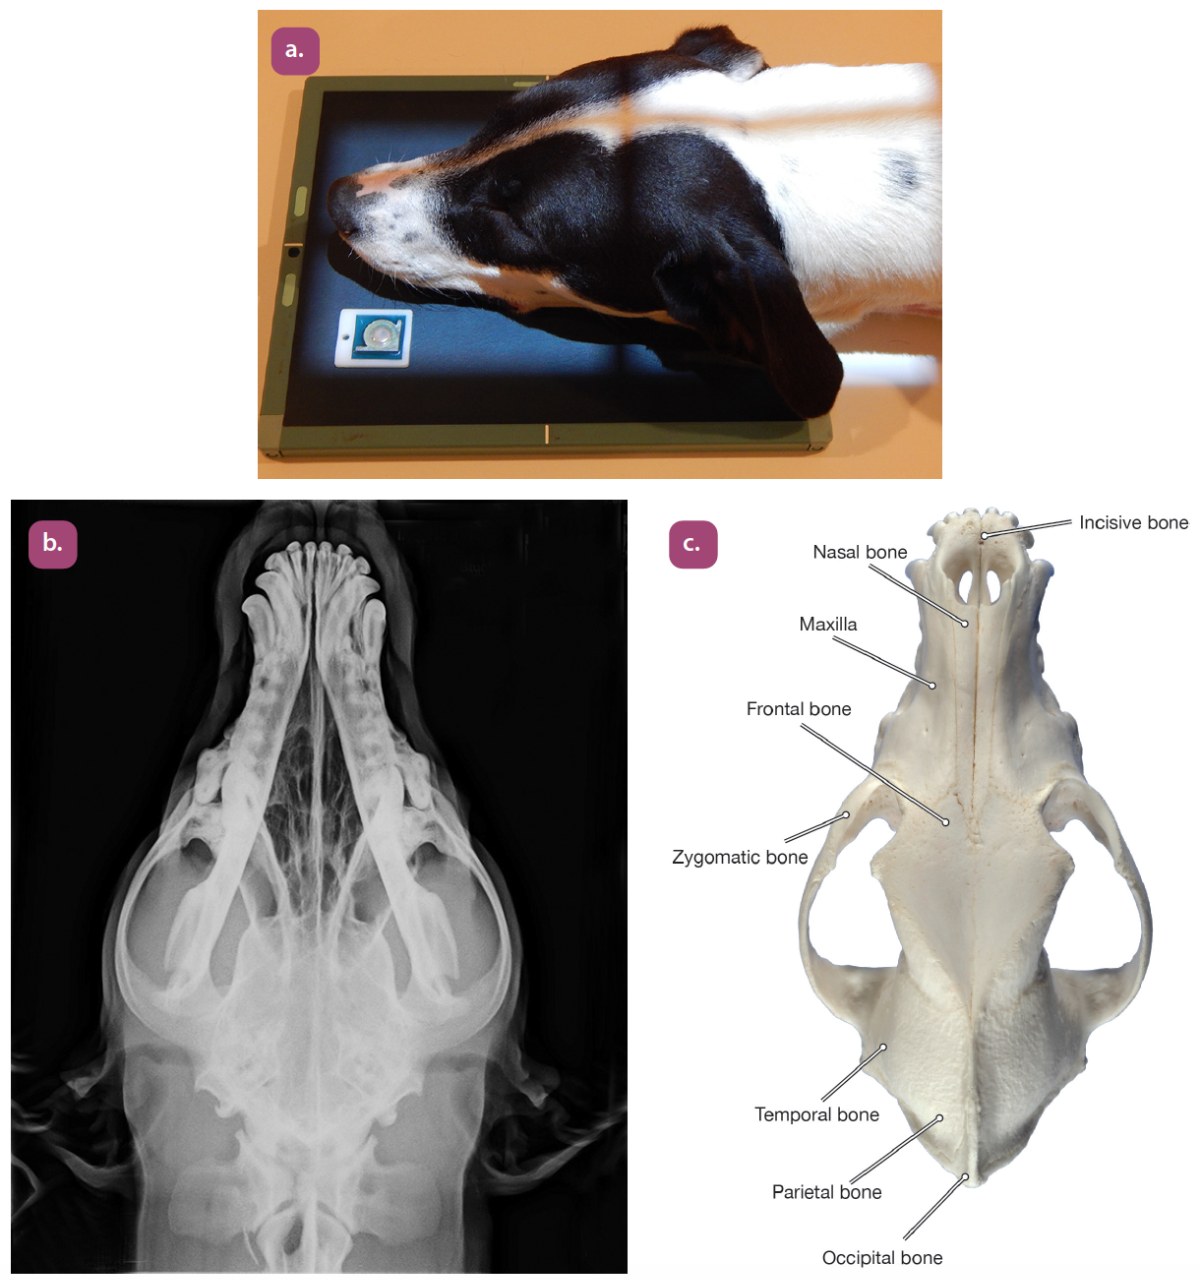

dorsoventral projection of the skull

ventrodorsal projection of the skull